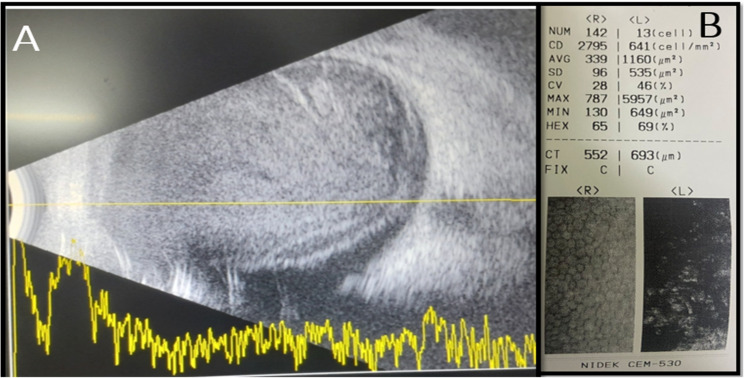

Case report: A 27-year-trekker male from an alpine climatic region of eastern Nepal was referred to our department, tertiary eye care in Nepal, with a history of sudden onset of redness, pain and decreased vision in his left eye following an indirect contact with a female Gazalina moth resting in his trekking bag during an ascent from 2,364 to 4,371 m above sea level. Circumcorneal congestion and cells, and flare were observed on clinical examination in the anterior chamber. A necrotising patch was present at the anterior sclera. The details of the lens, vitreous and retina were obscured because of hazy media. Ocular ultrasonography showed hyperechoic shadows in the vitreous with a thickening retina-choroid-sclera complex, suggestive of vitritis. He underwent treatment with antibiotics and steroids via all possible routes (topical, intraocular, periocular and systemic), and the scleral perforation could be prevented, but the visual rehabilitation was not possible.